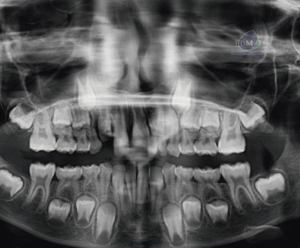

Paciente masculino de 81 años acudió al Instituto de Diagnóstico Maxilofacial (IDM) para una evaluación imagenológica general. En la radiografía panorámica (Figura 1) se identificó,